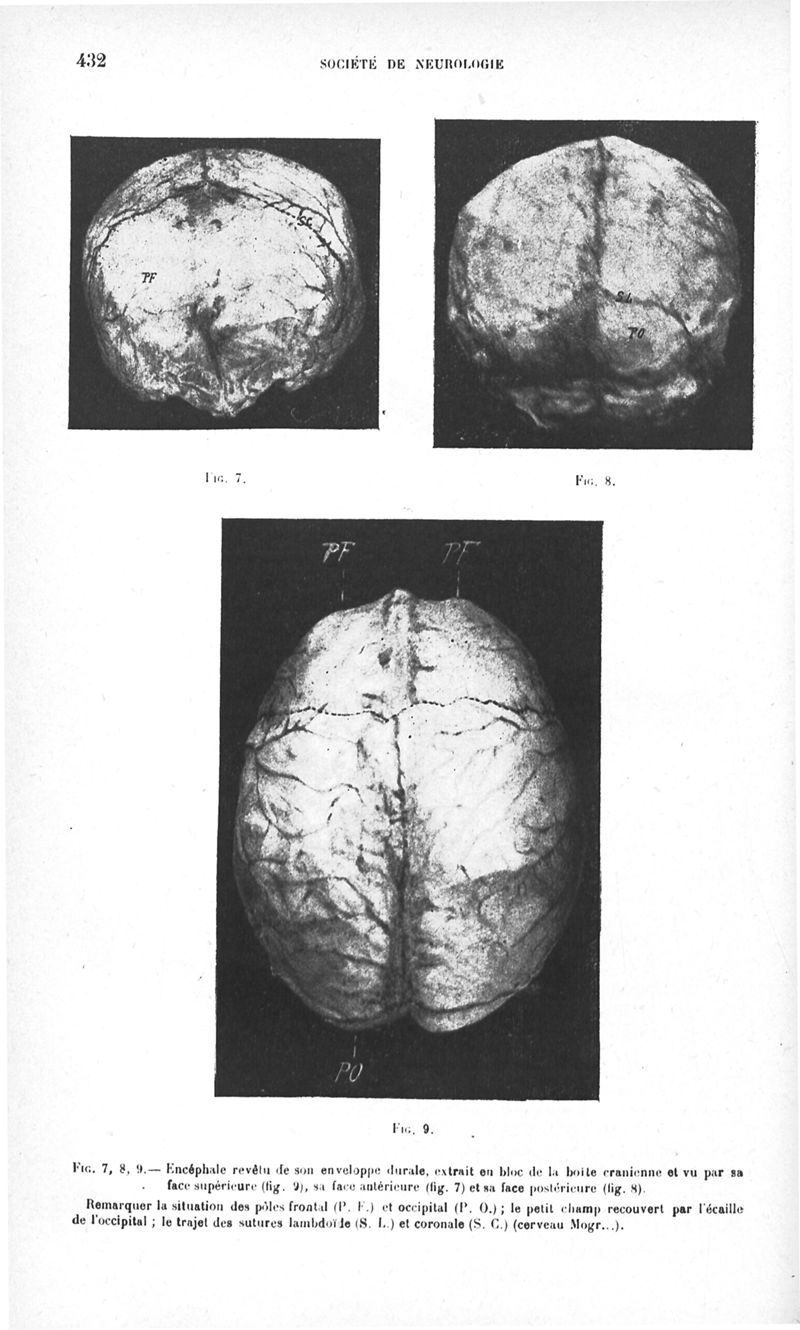

Revue neurologique

1916, vol 1. - Paris : Masson , 1916.